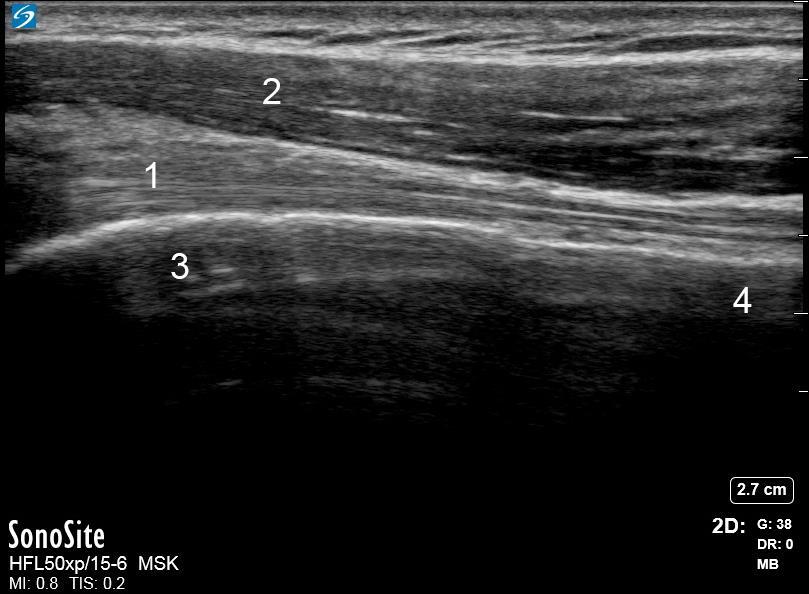

Image : Épaule : Antérieure, Coupe grand axe 3

1. Tendon du biceps

2. Muscle deltoïde antérieur

3. Tête humérale

4. Col de l'humérus